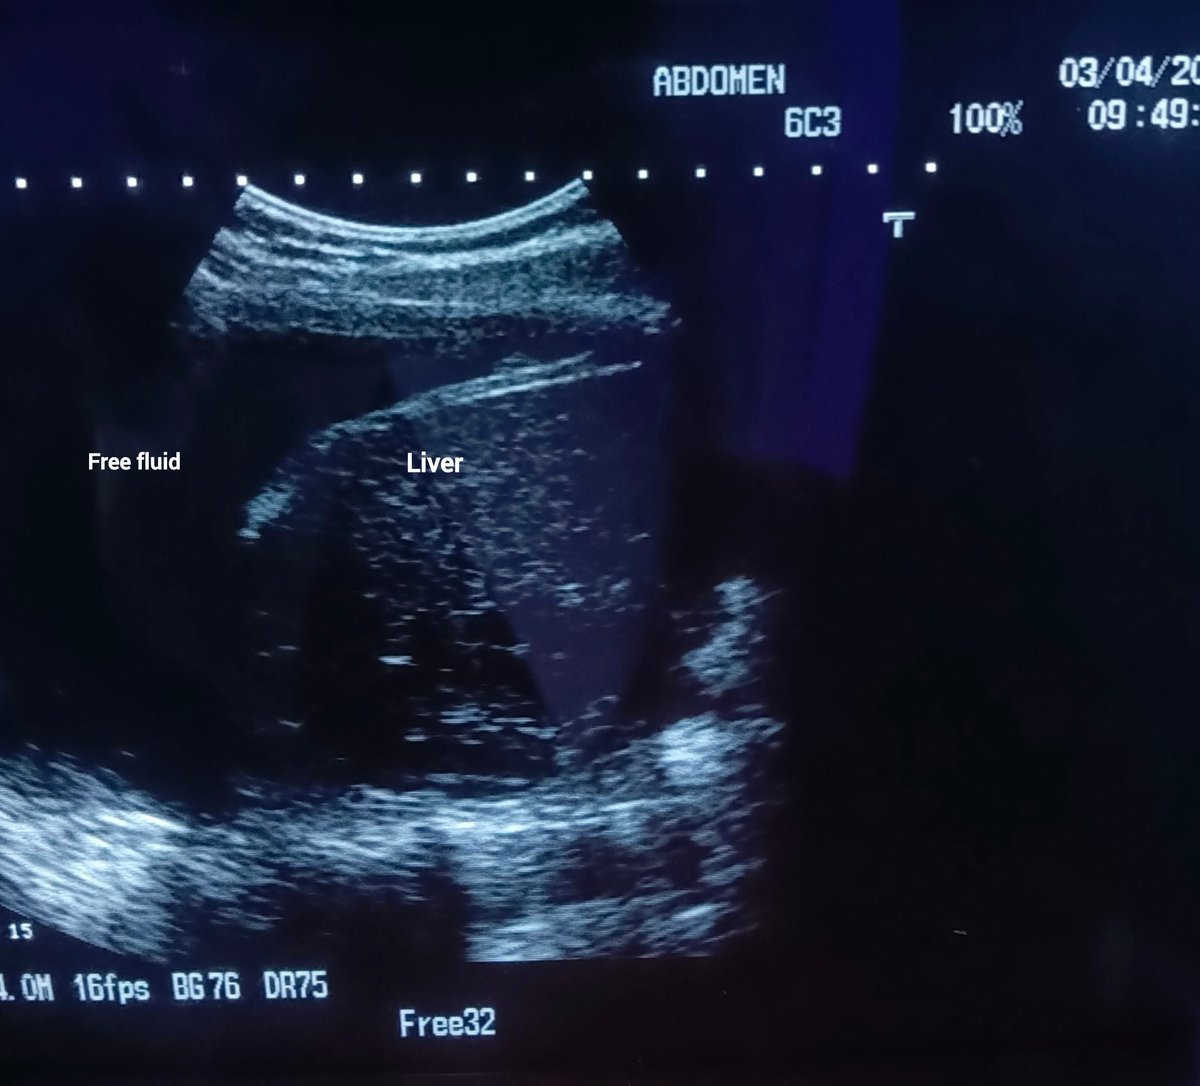

Liver feels firm and nodular upon palpation + Patient admits to decades of heavy social drinking. Spot Diagnosis??????

??????